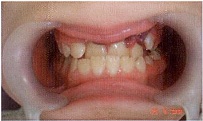

St. localis: гематома слизистой верхней губы, отек и гиперемия слизистой в области верхних резцов, гематома в области зубов 2.2, 2.3, обратное резцовое перекрытие в области 1.1, 2.1, 2.2. Экструзия зубов 1.1, 2.1 и 2.2, подвижность зубов 1.1, 2.1 и 2.2 II степени (Рис. 3).

Рис. 3

Окклюзия: смыкание в области первых моляров и клыков по III классу. Сужение и укорочение верхнего зубного ряда, по трансверзали бугровые контакты. Обратное

резцовое перекрытие около 3 мм. Вестибулярное положение зуба 2.3.